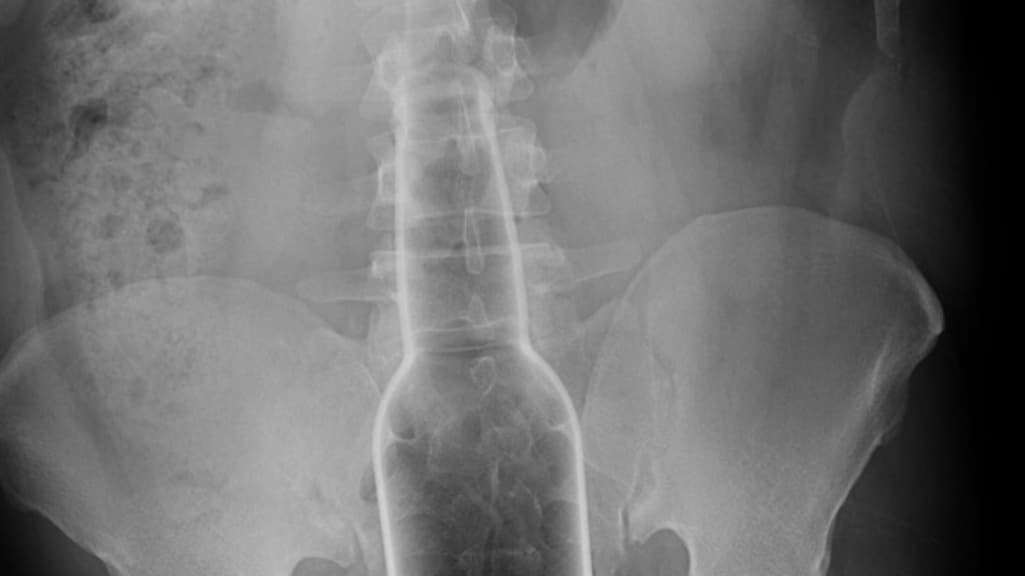

"Bierflesjes, wortels, tandenborstels, vazen en stenen, als het past, gaat het erin", zegt ze. Daar kunnen normen of richtlijnen weinig aan voorkomen. Wat wel zou helpen, is minder schaamte. De röntgenfoto's zijn afkomstig van een website voor en door artsen, waar zij foto's delen als naslagwerk.